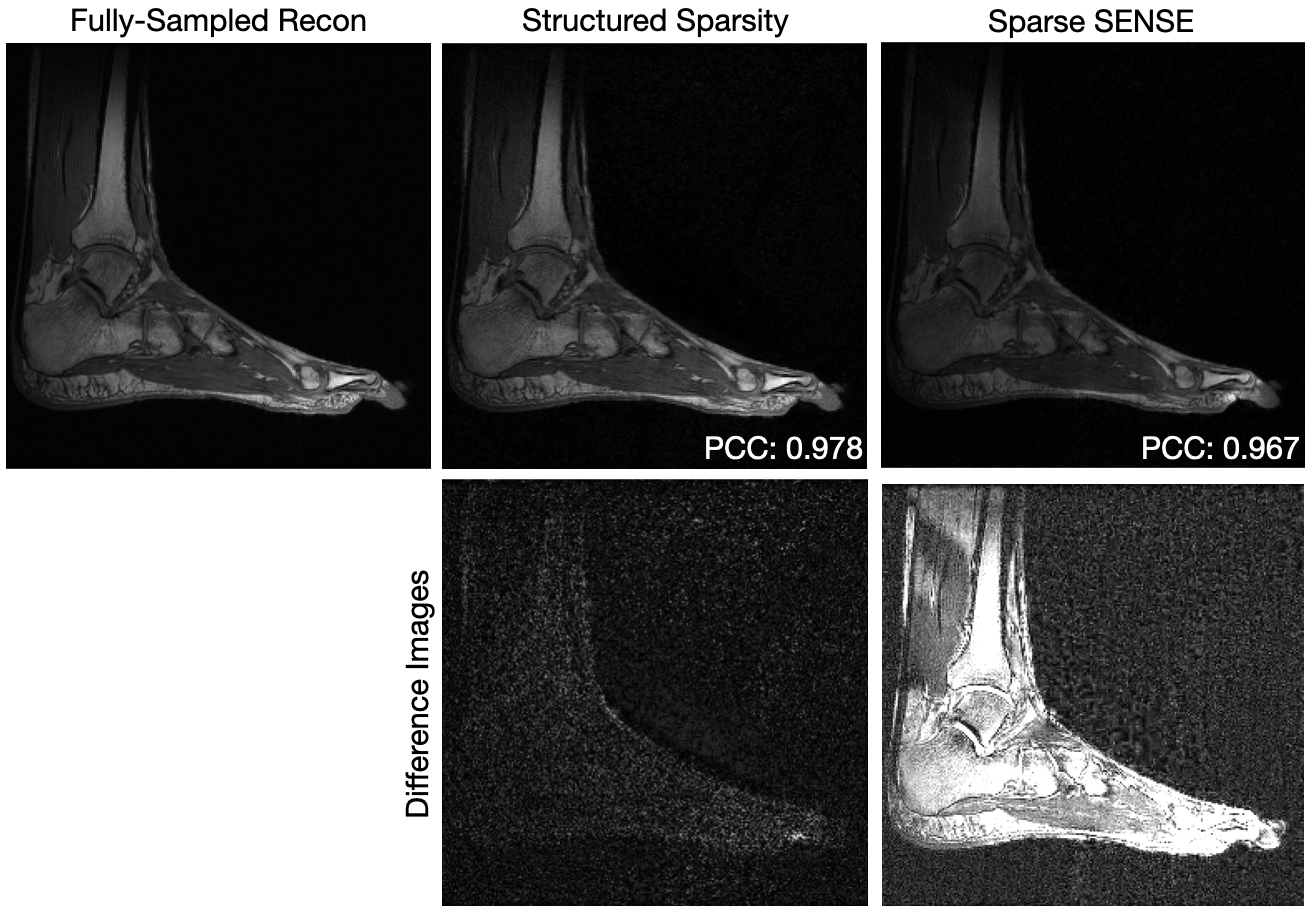

Figure 2 shows a comparison between the fully-sampled reconstruction, Sparse SENSE, and parallel imaging with compresses sensing using structured sparsity for data of a sagittal slice of an ankle collected with a 8-channel dedicated ankle coil array. The sampling pattern had an acceleration factor of 4.54.54.54.5 (i.e., only 22%percent2222\%22 % of the number of samples required to satisfy the Nyquist-Shannon sampling theorem were collected). For the ankle, the discrete Daubechies-4 wavelet transform was used as the sparsifying transformation [23]. The PCC values comparing the undersampled reconstructions and the fully-sampled reconstruction show that structured sparsity (PCC=0.9780.9780.9780.978) is more similar to the fully-sampled reconstruction than Sparse SENSE (PCC=0.9670.9670.9670.967). The difference images show that the errors in Sparse SENSE are not isolated to a small region, but instead, are spread throughout the image. Though the details remain visible with Sparse SENSE, the low-frequencies are highly corrupted.

Refer to caption

Figure 2: Comparison of fully-sampled reconstruction to reconstructions from accelerated acquisitions for a sagittal slice of an ankle with the compressed sensing with structured sparsity presented in this manuscript and the previously existing Sparse SENSE. The data collected had an acceleration factor of 4.54.54.54.5. Differences with a fully-sampled reconstruction are shown on the same intensity scale. The Pearson Correlation Coefficient (PCC) is displayed for each reconstruction. Difference images are shown on the same scale.